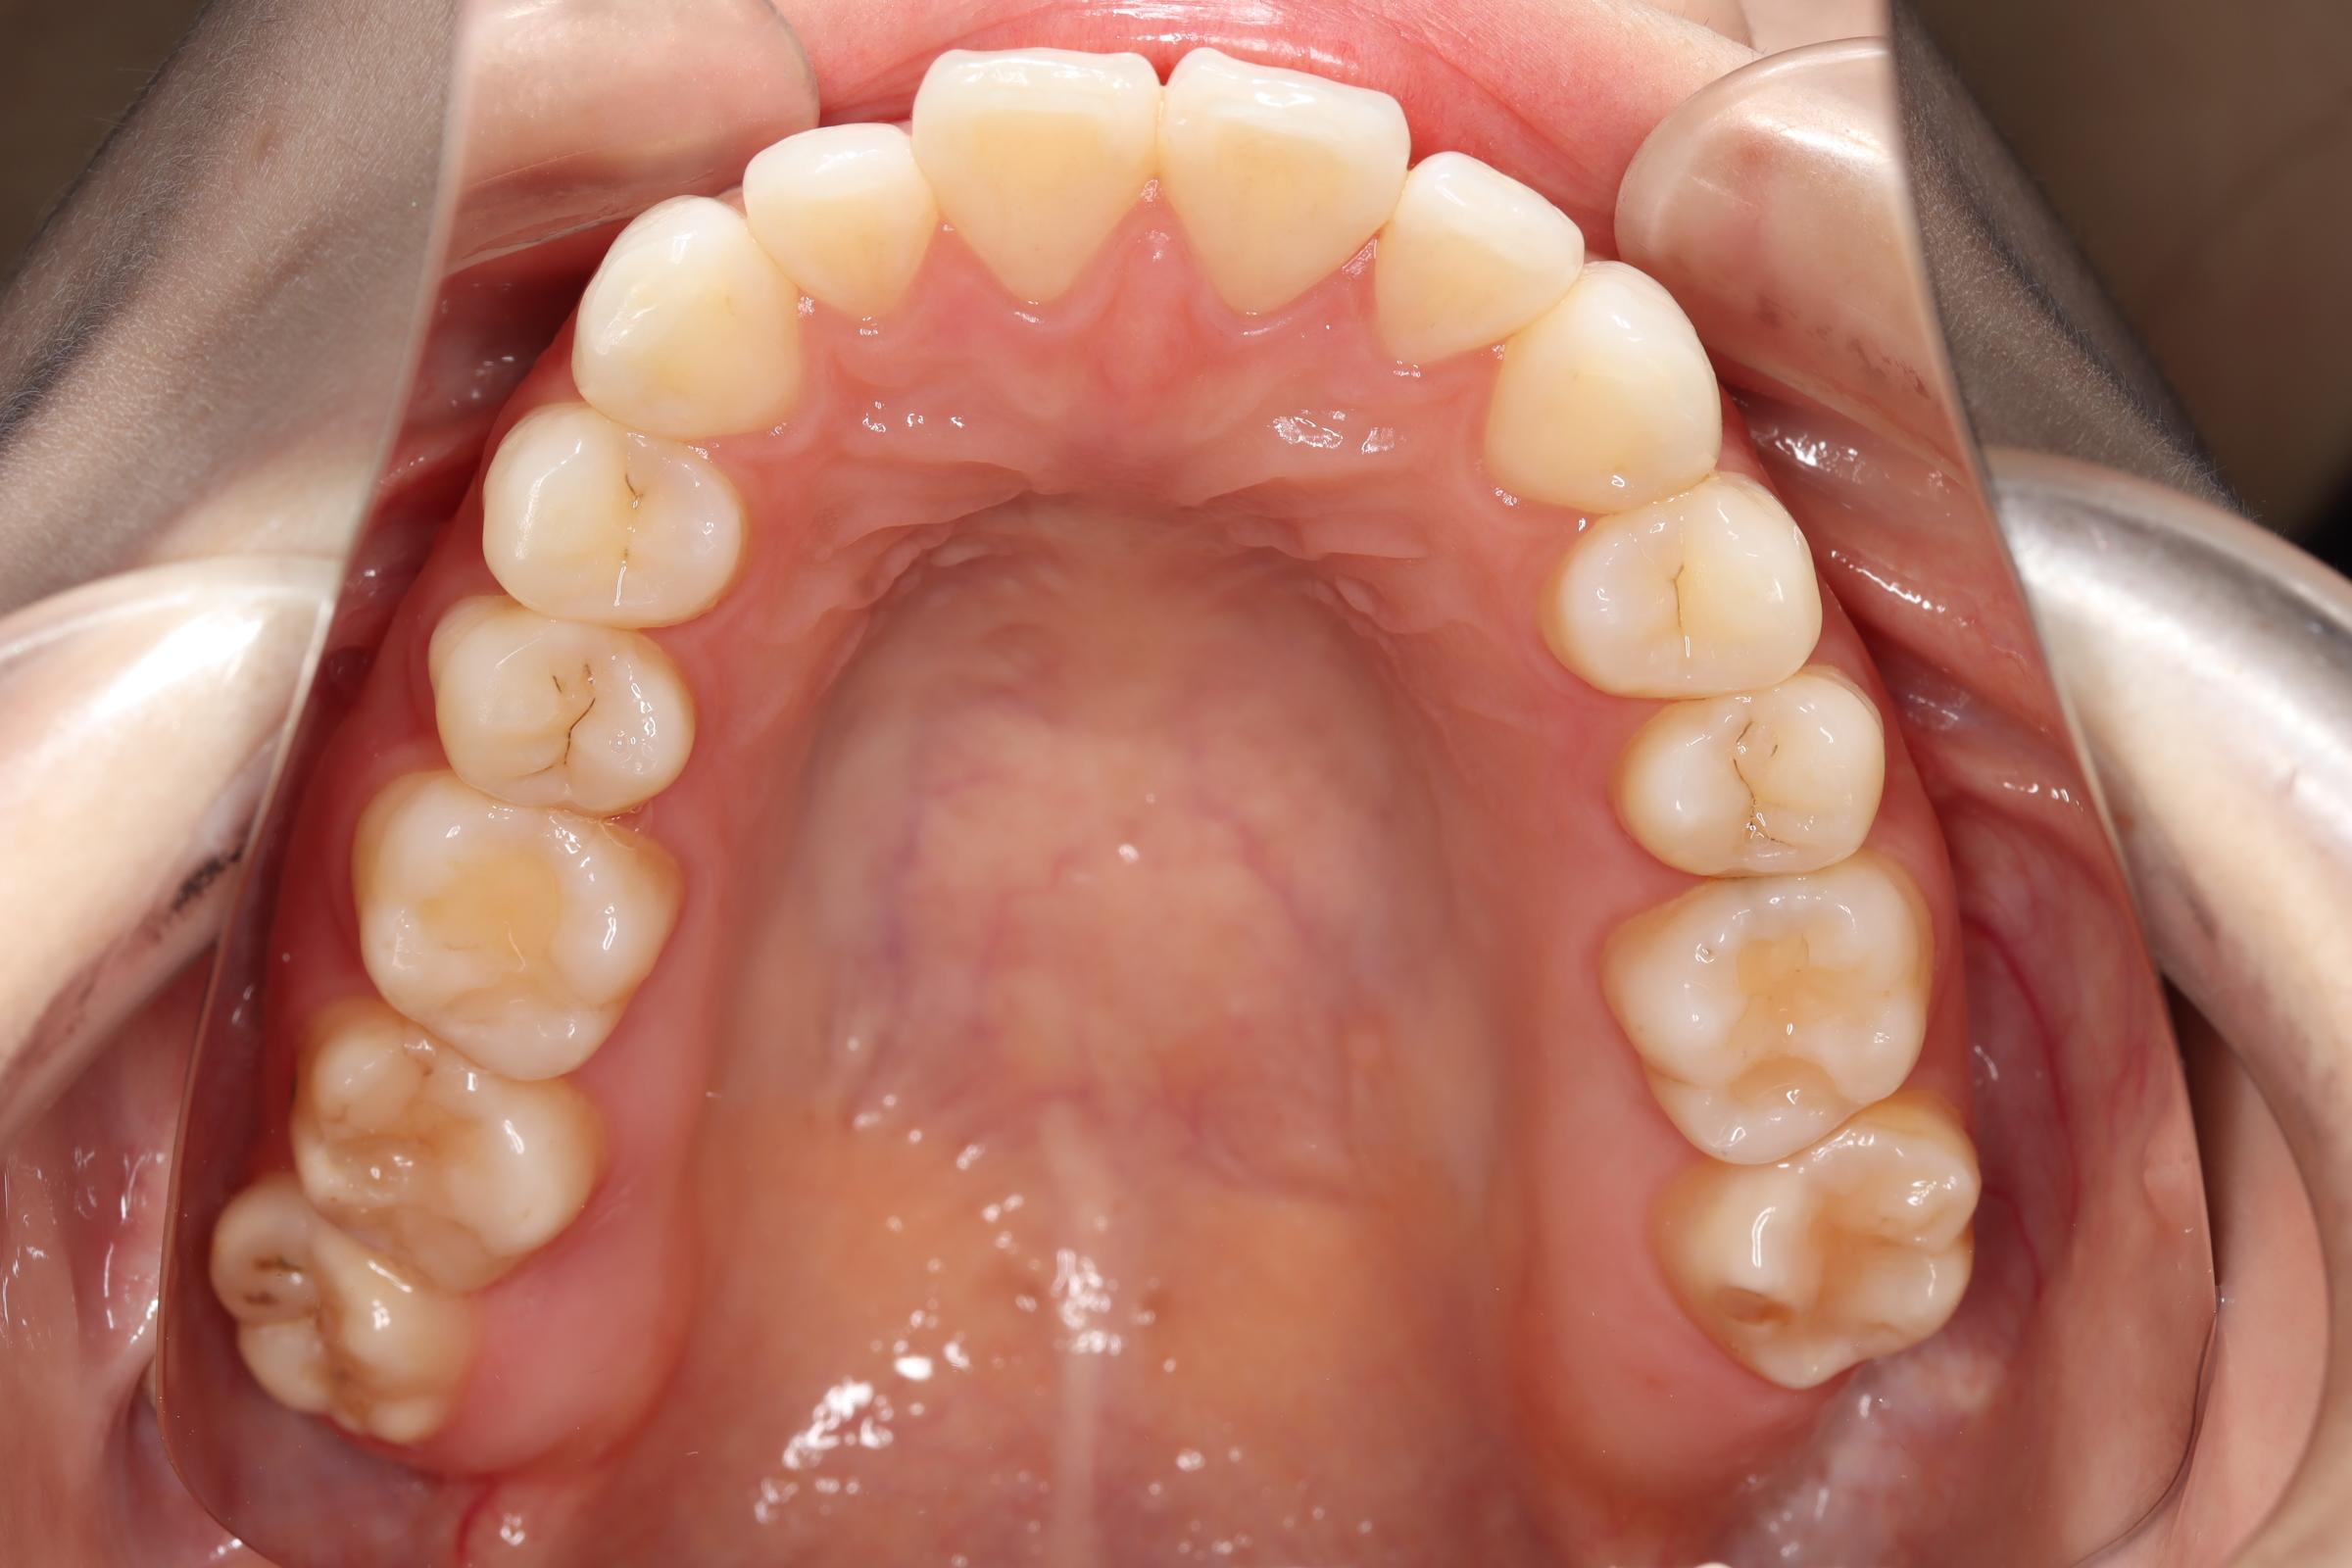

口腔内の変化

![]() | ![]() | ![]() |

| ↓ | ↓ | ↓ |

治療前後の解説

| 治療前 | 骨格的には受け口の患者さんですが、上顎前歯の唇側傾斜が大きく、患者さんとしては出っ歯だと思われていたパターンです。 元々口元の突出感はほとんどなかったため、歯を抜かずに上下顎ともに歯列を後方に移動させることにより主訴を改善させることとしました。 |

| 治療後 | 前歯から奥歯まで全体的に緊密な咬み合わせになっています。 治療前後のセファログラムのトレースの重ね合わせを比較すると、上下の歯列の後方移動ができ、それにより口元もよりすっきりしました。 また前歯の唇側傾斜も改善されています。 |